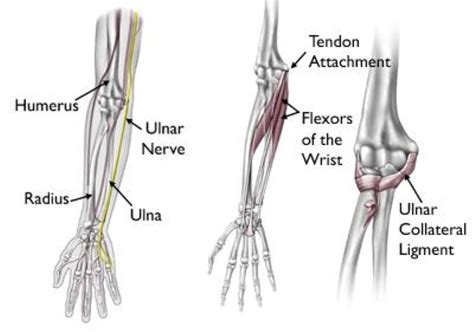

Ulnar Collateral Ligament (UCL) Injuries

The UCL is a ligament on the inside of your elbow that provides stability. It’s a key player in the throwing motion. Softball elbow injuries involving the UCL can range from minor sprains to complete tears. This can happen from a single, forceful throw or from the cumulative effects of repetitive stress. The symptoms can vary, but often include pain on the inner side of the elbow, a popping sensation during throwing, and a feeling of instability. UCL injuries are often more serious and may require surgery, especially if the tear is severe. Early diagnosis and treatment are crucial to avoid long-term complications. The recovery period after surgery can be lengthy, so prevention is always the best approach. Guys, protecting your UCL is super important!